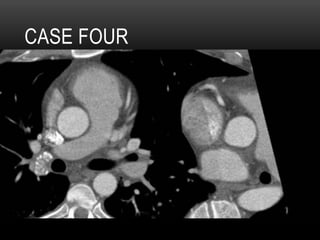

CASE 4

•  32 yr old male

•  Atypical CP, equivocal stress echo

•  Cath: “No vessel coming off R sinus”, concern

for anomalous coronary artery

CASE FOUR

QUADRICUSPID

AORTIC VALVE